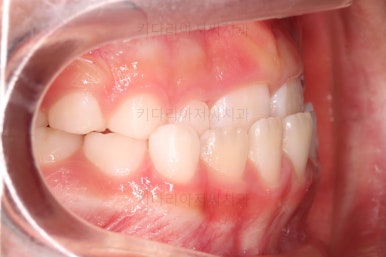

치료 6개월째입니다.

반대교합은 잘 개선되었는데요.

혀/입술 근육 훈련을 위해서 더 사용하기로 했으며 마침 윗니 작은 앞니도 맹출하는 중이라 해당 치아의 맹출 경로를 안내해 주는 역할로 프리올소를 더 사용하기로 했습니다.

치료의 진전과 함께 또 다른 혹은 향후 유지에 적합한 프리올소를 하나 더 제공하고요.

부산어린이교정 키다리아저씨치과에서 앵글씨 3급 부정교합 및 반대교합이 잘 개선되었습니다.

심지어는 치열을 정교하게 맞추는 기능이 있는 장치는 아니지만, 자연스럽게 맹출 경로를 잡아줌으로써 앞니 치열도 매우 고른 양상이 되었습니다.